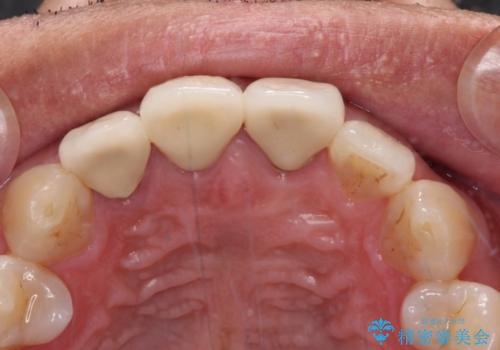

変色した歯はきれいになり、両隣の歯とも自然に馴染み、ご家族からも好評で大変満足されました。